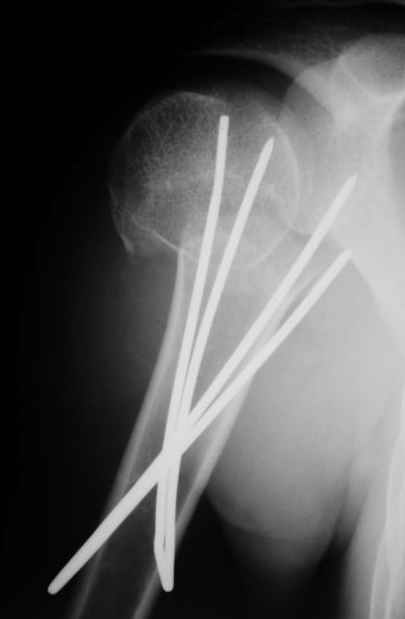

Клинические снимки - 3 недели после операции

с уважением М. Беренштейн

Посылаю послеоперационные Рг граммы.

Всего Доброго,

Евгений И Чекашкин

Поздравляю, получилось просто замечательно. Если можно, расскажи чуть подробнее, как делали - как вправляли, как вводили спицы, поворачивали ли их?

|